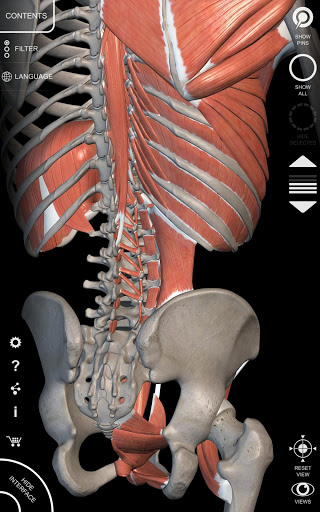

"Anatomy 3D Atlas" дозволяє легко та інтерактивно вивчати анатомію людини.

Завдяки простому та інтуїтивно зрозумілому інтерфейсу можна спостерігати кожну анатомічну структуру під будь-яким кутом.

Анатомічні 3D-моделі особливо деталізовані та мають текстури з роздільною здатністю до 4k.

АНАТОМІЧНІ 3D МОДЕЛІ

• Кістково-м’язова система

• Обертайте та збільшуйте кожну модель Тривимірний простір

• Можливість приховування або ізоляції однієї чи кількох вибраних моделей

• Фільтр, щоб приховати або відобразити кожну систему

• Візуалізація м’язів через рівні шарів від поверхневих донизу до найглибших